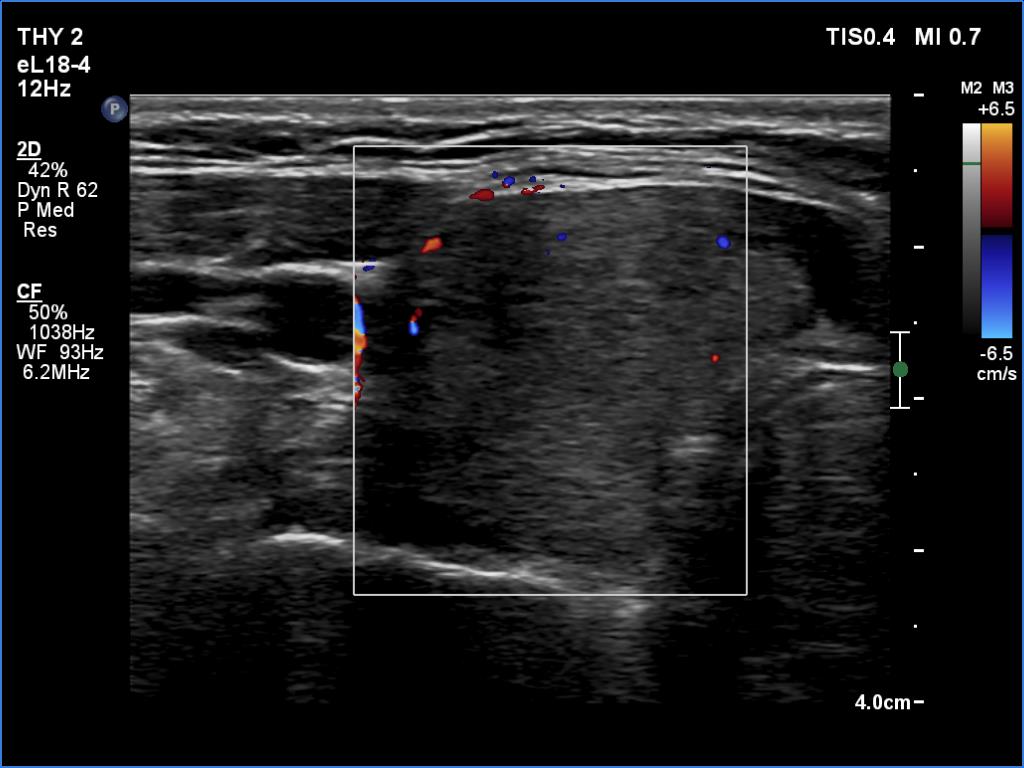

Ultrasonography. The thyroid was echonormal and inhomogeneous and presented hypoechoic areas. The echogenicity index was around 30-35%. The vascularity was decreased on Doppler mode.

Except for early phase of a recurrent hyperthyroidism, the vascularity is almost always increased in the event of overproduction, i.e. in Graves' disease. In the event of hyperthyroidism caused by thyroiditis, the vascular pattern is not characteristic, it can be either increased or decreased.